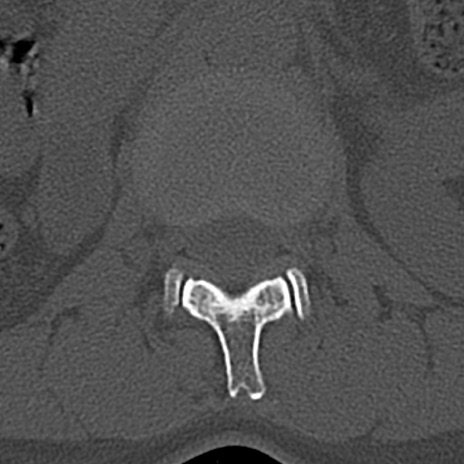

【整形】TIPS症例4 腰椎CT(横断像)

腰椎CT

横断像と矢状断像